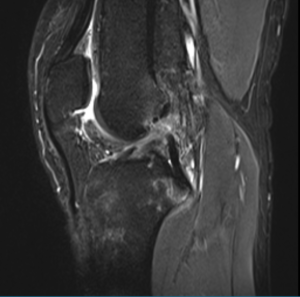

Diagnosis

An ACL injury can be diagnosed with a thorough physical examination of the knee and diagnostic tests such as X-rays, MRI scans and arthroscopy. X-rays may be needed to rule out any fractures. In addition, your doctor will often perform the Lachman’s test to see if the ACL is intact. During a Lachman test, knees with a torn ACL may show increased forward movement of the tibia and a soft or mushy endpoint compared to a healthy knee.